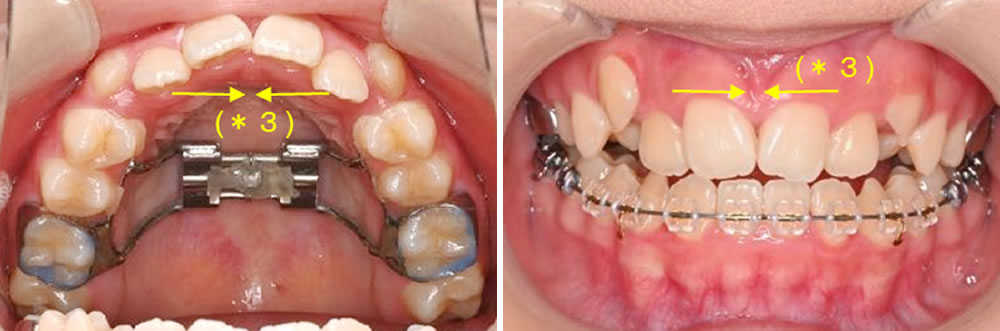

【矯正開始から3ヵ月:前歯部空隙の自然閉鎖】

(*3)とても気になる前歯の隙間ですが、歯は隙間があると寄っていく性質があり、装置をつけていなくても自然と前歯が寄ってきて、前歯のすき間が閉じてきます。

その後、上顎歯列にマルチブラケット装置を装着してワイヤー矯正を進めました。